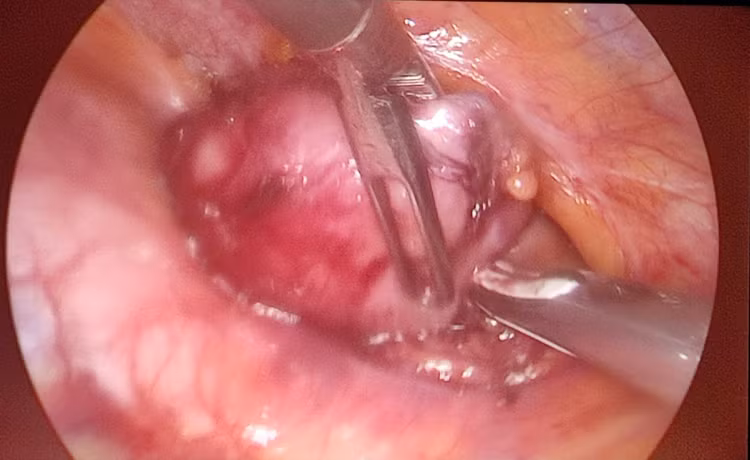

Qua các vết rạch nhỏ vào khoang màng phổi phải, phẫu thuật viên đưa dụng cụ nội soi vào tỉ mỉ phẫu tích, bóc tách và cắt toàn bộ tuyến ức kèm khối u. Sau khoảng hơn 30 phút thực hiện, toàn bộ tổ chức tuyến ức và khối u tuyến ức kích thước khá lớn đã được cắt bỏ hoàn toàn và lấy ra ngoài mà không gây mất máu.

| Hình ảnh khối u tuyến ức qua nội soi được kíp phẫu thuật bóc tách - ảnh BSCC |